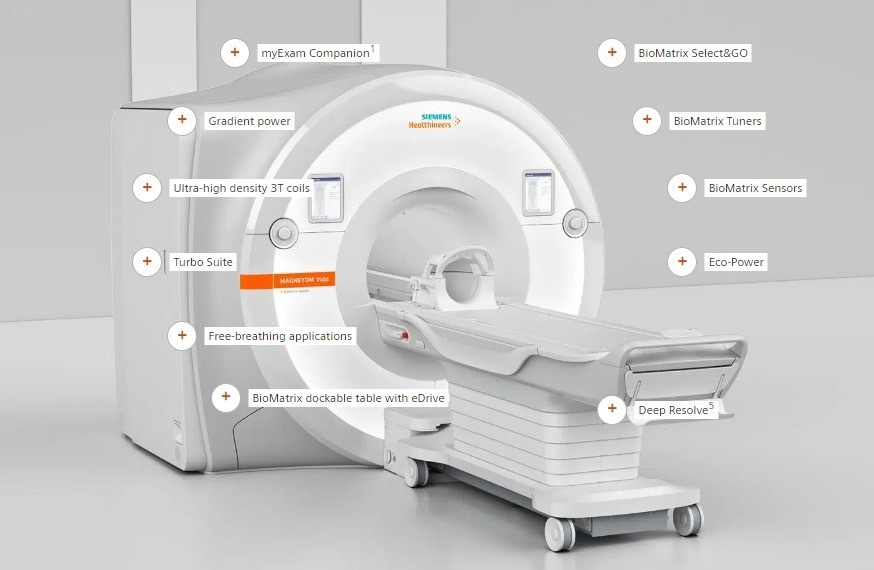

MAGNETOM Vida – the first 3T MRI scanner with BioMatrix Technology – embraces human nature and the unique challenges that each patient brings to the MRI exam. By embracing these challenges, patient variability an be overcome – ushering in a paradigm shift in MRI. The outcome results in a lower number of rescans, predictable scheduling, and consistent, high-quality personalized exams for high-end clinical routine as well as clinical research.

- Embrace full 3T performance with unparalleled magnet and gradient power

- Embrace true 3T productivity with Turbo Suite and myExam Companion1

- Embrace new 3T clinical capabilities with Inline Compressed Sensing

MAGNETOM Vida. Embrace human nature at 3T. Image Credit: Siemens Healthineers.

Features and benefits

myExam Companion1

Gradient power, with up to 60/200, simultaneously with 11,000 hp amplifier power

Ultra-high density 3T coils

Turbo suite

Free-breathing applications with Inline Compressed Sensing (available in Turbo Suite Elite)

BioMatrix dockable table with eDrive assistance and AutoDocking

Deep Resolve5

Efficient energy management with Eco-Power